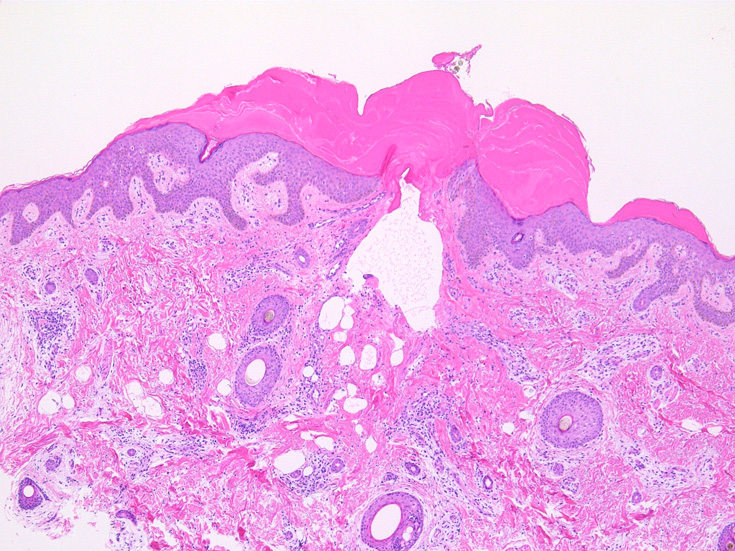

IWT-case01 66yo male. 3週間前(!)南アルプスに登山. 腹部皮膚のイボ様腫瘤に気づき来院。

マダニと思われる虫体を皮膚ごと切除した。

マダニ科マダニ(4属)では触肢と口器は短くなっており,そのために, 吸血後24時間程度経過すると,唾液腺で産生されるセメント様物質を分泌して口下片全体を包みこみ,体を宿主にしっかりと固定する.

(case02の皮膚表面にみられる硝子様の層がそれに相当するようです。)